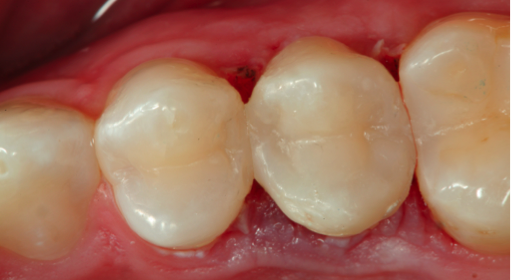

Bulk-Fill Flowable Composite as a Dentin Replacement

After the caries is removed, the tooth is isolated. The placement of the band using a sectional matrix to restore the proximal contour and contacts is critical. After application of the adhesive, the bulk-fill flowable and composite capping layers are placed and light-cured, and the matrix band is removed. The contact is so tight when using a sectional matrix that removal often requires a hemostat. Note the identical height of the restored marginal ridge as compared to adjacent tooth (Figure 9). This accuracy is due to the careful placement of the matrix to limit the amount of finishing and polishing that will need to be done to complete the restoration.

Figure 9. The identical height of the restored marginal ridge as compared to adjacent tooth due to the careful placement of the matrix.

Figure 9